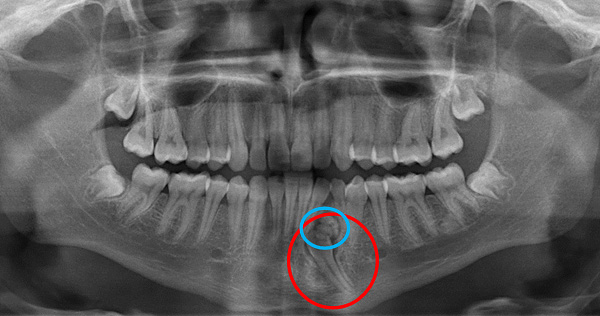

Дентальная галерея: ретинированный зуб клык и его лечение

Раздел: Компас решений